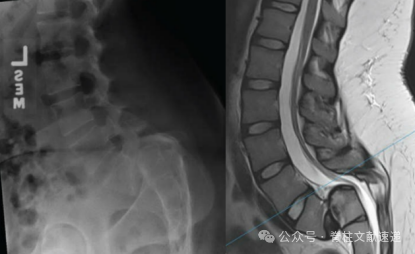

重度腰椎滑脱是指滑移程度>50%的椎体滑脱,是脊柱外科最高难度的手术之一。关于该病的治疗策略有原位融合和复位融合。在此简要介绍复位固定技术和原位固定技术。

左图为失平衡型腰椎滑脱,L5I>45度,骨盆后倾,腰椎前凸不能代偿L5-S1后凸,上端椎相对S1前移。右图为平衡性腰椎滑脱,L5I<45度,骨盆倾斜角正常,腰椎前凸能够代偿,上端椎位于骶骨上。平衡性重度腰椎滑脱可考虑原位融合。

这里有一个很重要的角度,L5滑脱角,指L5上或下终板与骶骨后缘的夹角,这个角度越大,局部后凸越大,往往存在S1明显穹窿,越需要复位融合。